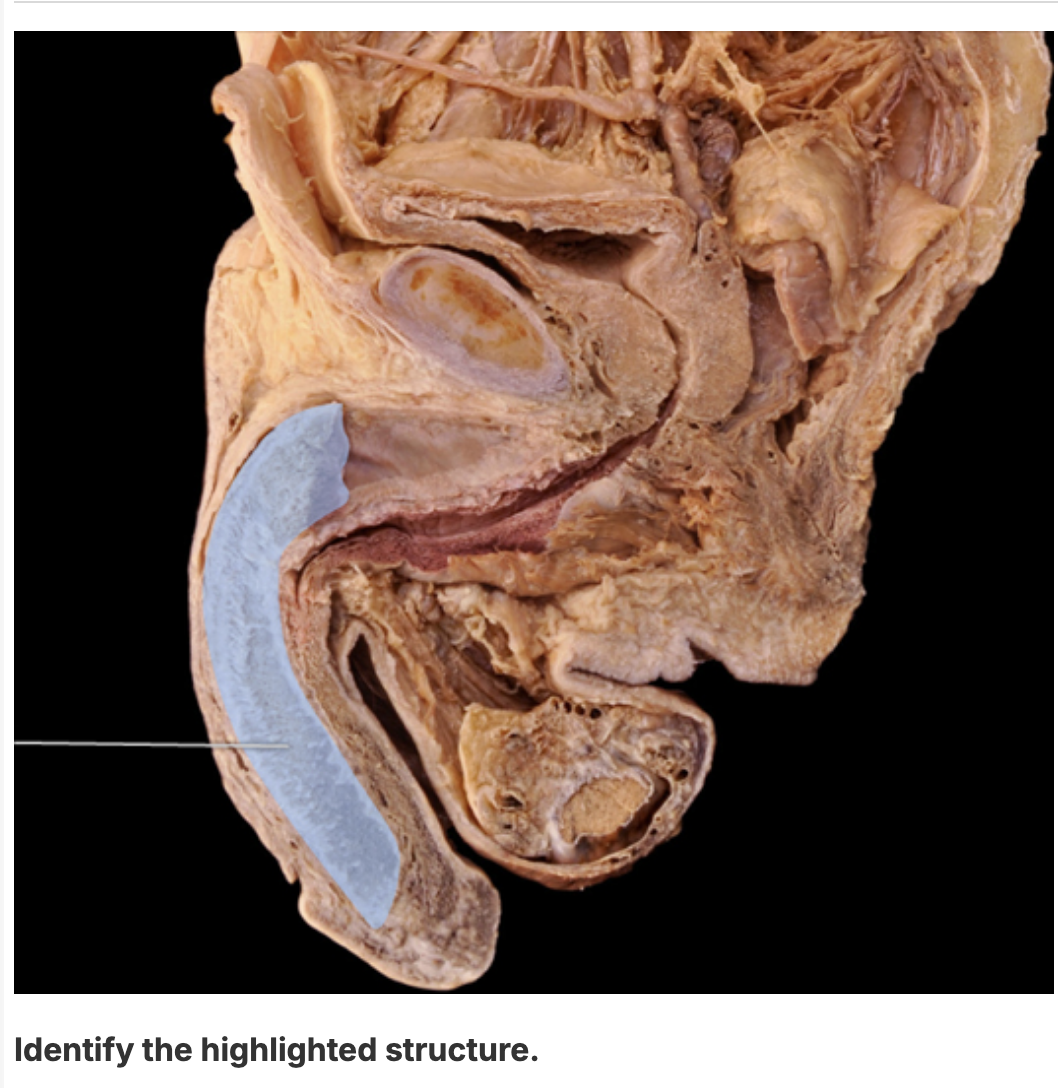

penis

corpus cavernosum

corpora cavernosa